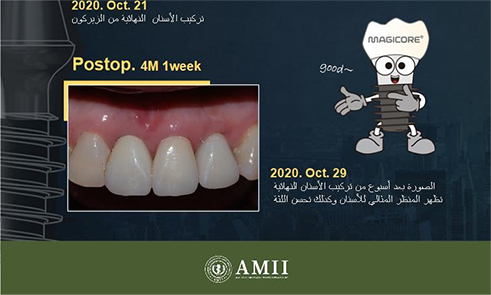

Explore the tangible results of our dedication. Each Tooth is a unique story of transformation and renewed confidence.